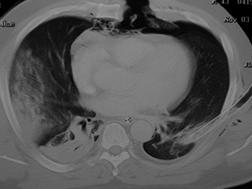

Imagine

CT Imagine CT

Pneumotorace deschis Pneumotorace

Contuzie pulmonara stanga Contuzie pulmonara dreapta

Contuzie pulmonara dreapta.Imagine CT